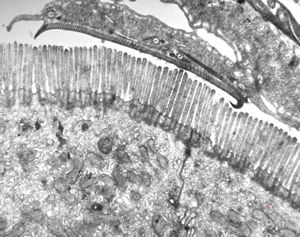

normal mucosa - jejunum - microvilli(anchored core rootlets)

normal mucosa - jejunum - microvilli